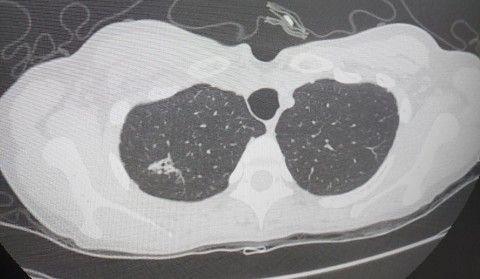

폐ct에 하얀덩어리가 보이는데 뭘까요?

하얀덩어리 있는게 왼쪽폐맞죠?

10년전에는 좀 더 작았는데 점점 커지는것같아서요

대학병원에서 기관지내시경도 해보고 ct도 찍었는데 잘모르겠다고 하셔서요 암은 아니시라고 하는데

1. 하얀 폐 병변이 있는 곳은 왼쪽이 아닌 오른쪽 폐입니다.

2. 해당 CT 사진만 가지고 구체적으로 어떠한 병변인지 명확하게 파악하기는 어렵습니다.